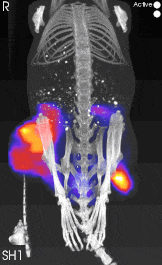

Figure2. 注射NIR探針后的小鼠掃描圖像